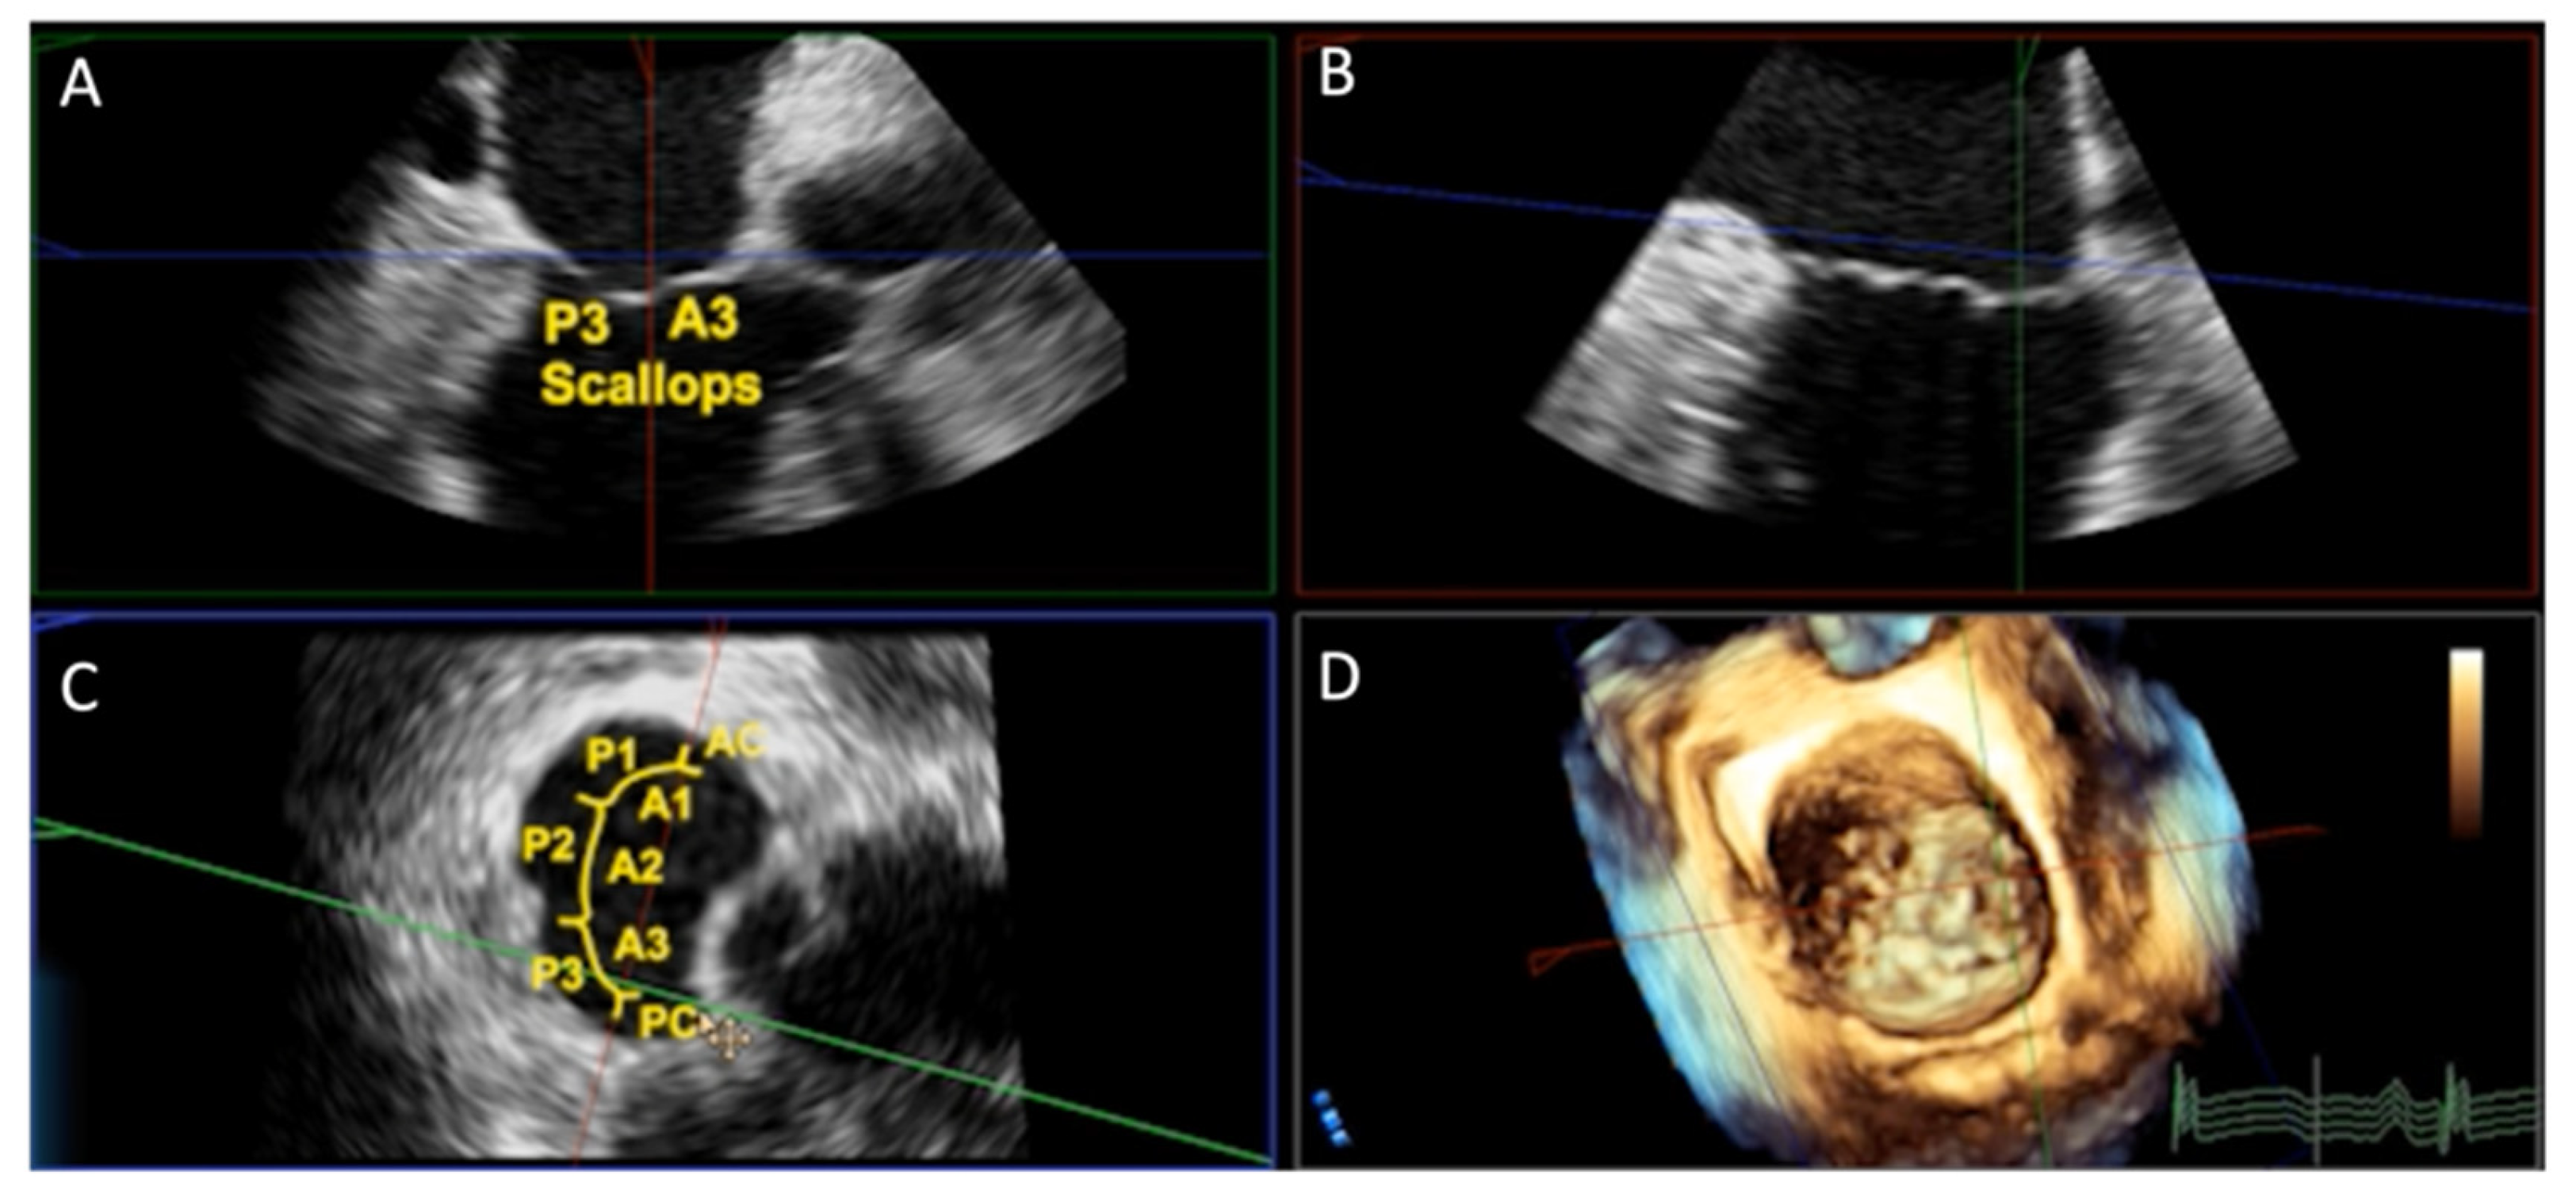

2.1. TEE Evaluation of the Mitral Apparatus

4.1. TEE with Multiplanar Reconstruction

- Faza, N.N.; Little, S.H. Role of 3-dimensional transesophageal echocardiography in guiding transcatheter mitral valve replacement. Echocardiography. 2020, 37, 945–953. [Google Scholar] [CrossRef] [PubMed]